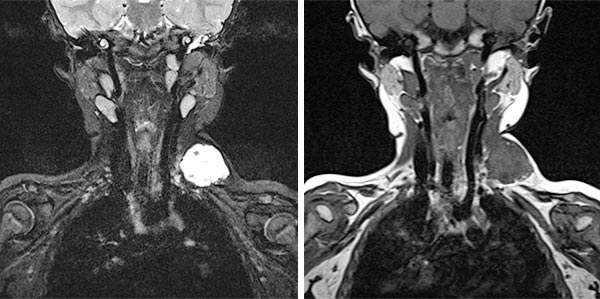

In coronal MRI (left image: T2-weighted, right image: non-enhanced T1-weighted), the venous malformation (VM) is very well delineated. It is strongly hyperintense in the T2 image, whereas it is isointense to the musculature in the non-enhanced T1 image. The signal intensity is typical of the character of a slow-flow lesion.

In coronal MRI (left: T2-weighted, right: T1-weighted non-enhanced) slightly more dorsally, a larger thrombus within the venous malformation is very well delineated. In the T2 image, this is hypointense compared to the severely hyperintense venous malformation. In the non-enhanced T1 image it is slightly more hyperintense than the surrounding hypointense venous malformation.